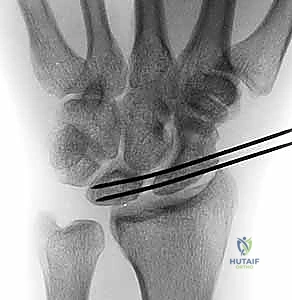

K-wire Fixation: Once an optimal reduction is achieved, we will temporarily stabilize the scaphoid and lunate using K-wires.

- Typically, we'll insert two 0.045-inch or 0.062-inch K-wires.

- One K-wire will pass from the scaphoid into the lunate, traversing the reduced scapholunate interval.

- A second K-wire will pass from the lunate into the triquetrum, or from the scaphoid into the capitate, to further stabilize the carpus and maintain the reduction.

- Ensure the K-wires are placed to avoid future tunnel drilling sites and are not impinging on articular surfaces.

Surgical Warning: K-wire placement must be precise. Avoid violating the midcarpal or radiocarpal joint spaces. Confirm placement with multiple fluoroscopic views (PA, lateral, oblique) to ensure proper carpal alignment and avoid iatrogenic injury. Overtightening the reduction can lead to stiffness; aim for a stable, anatomical reduction.

TECH FIG 3 • A. K-wires are used to reduce the scapholunate interval.